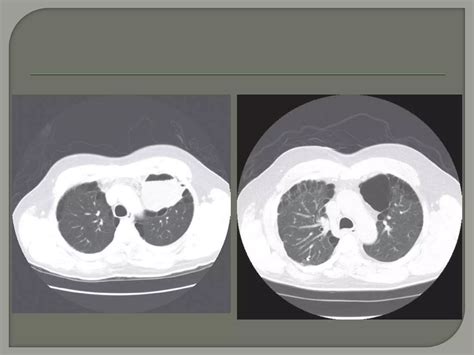

Diagnostic Procedures

Diagnosis begins with a thorough medical history and physical examination. However, imaging is essential to confirm Bullous Lung Disease. High-resolution Computed Tomography (HRCT) is considered the gold standard for visualizing bullae. It allows physicians to determine if the bullae are localized or widespread and whether they are compressing functional lung tissue. Pulmonary function tests (PFTs) are also conducted to measure lung capacity and identify the degree of airflow obstruction.

• Bullectomy: A surgical procedure to remove large, non-functional bullae that are compressing healthy lung tissue.

💡 Note: Surgical interventions are generally reserved for patients where the bullae occupy more than one-third of the hemithorax and are causing significant, symptomatic compression of healthy lobes.

While often associated with emphysema, bullae can develop through various mechanisms. The lung tissue essentially loses its internal architecture, leading to areas of over-inflation. When these areas become large enough to compress healthy surrounding tissue, the condition is referred to as giant bullous emphysema, or Vanishing Lung Syndrome, in extreme cases.